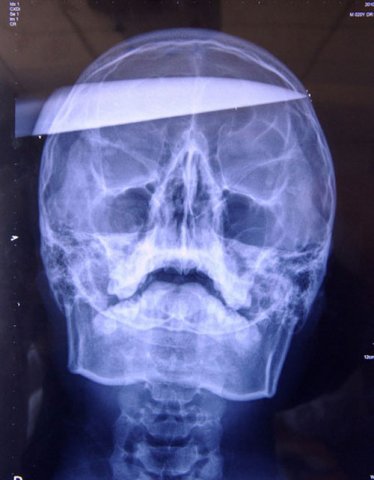

Auf dem Bild kann man deutlich erkennen, dass das Messer fast auf der anderen Seite herausgekommen währe. Aber der 17jährige hat Überlebt, da keine wichtigen Arterien verletzt worden sind und er damit nicht verblutete. Leider durchtrennte das Messer teile vom Gehirn, was für die motorischen Fähigkeit verantwortlich ist, aber durch Zufall wurden beim Opfer keinerlei motorische Beeinträchtigungen festgestellt. Er wurde sogar mit vollem Bewusstsein ins Krankenhaus eingeliefert.

Das Opfer ist weiterhin noch im Krankenhaus unter Beobachtung, da man die Befürchtung hat, dass sich Rost vom Messer gelöst hat. Laut dem Arzt Yan Shi-Jun, der das Messer entfernt hat, liegt die Wahrscheinlichkeit, dass man bei solch einen Angriff überlebt Eins zu Zehntausend.